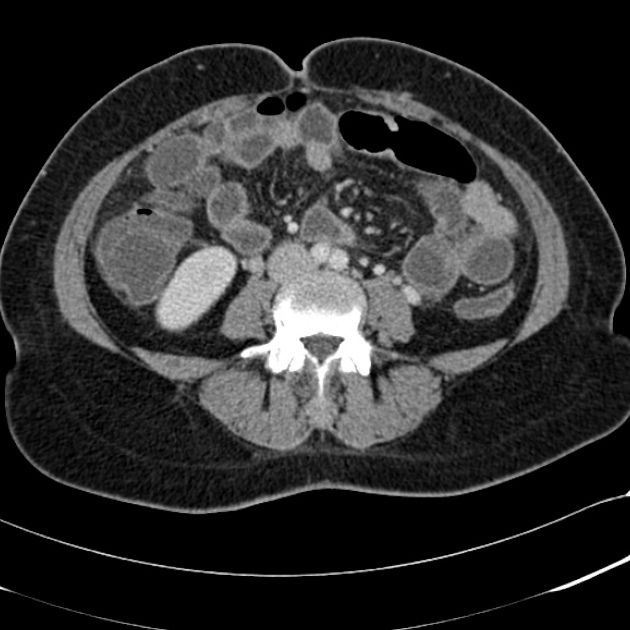

Following are the contraindications of CAT Scan: - Pregnant - History of reaction to contrast agents - Renal disease Reference: https://www.aafp.org/afp/2013/0901/p312.html#:~:text=Possible%20contraindications%20for%20using%20intravenous,or%20acutely%20worsening%20renal%20disease. Image via: https://radiopaedia.org/cases/acute-appendicitis-38